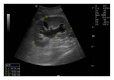

Renal transplantation is the treatment of choice for managing patients with end-stage kidney disease. Being submitted to a very serious surgical procedure, renal transplant recipients can only benefit from follow-up imaging and monitoring strategies. Ultrasound is considered as the principal imaging test in the evaluation of renal transplants. It is an easily applied bedside examination that can detect possible complications and guide further imaging or intervention. In this imaging review, we present essential information regarding the sonographic features of healthy renal transplants, detailing the surgical technique and how it affects the sonoanatomy. We focus on various complications that occur following renal transplantation and their sonographic features by reviewing pertinent literature sources and our own extensive imaging archives.